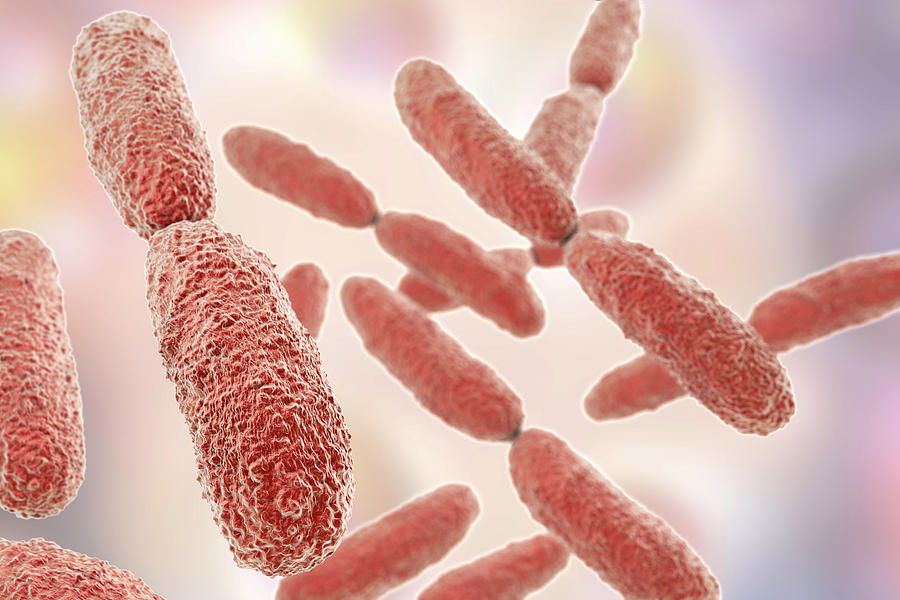

Фотографии бактерий, вызывающих бактериальные пневмонии у животных